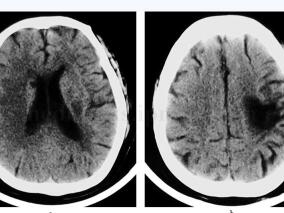

1小时条评论【病例摘要】 老年男性患者因肺栓塞使用华法林、低分子肝素钙治疗,华法林剂量从3mg逐渐增至5.25mg,低分子肝素钙首剂量4100IU后使用6150IU,q12h皮下注射。19天后患者出现喷射性呕吐,头颅CT示脑出血,破入脑室,出血量约30ml,凝血检查示国际标准化比值为1.92。...